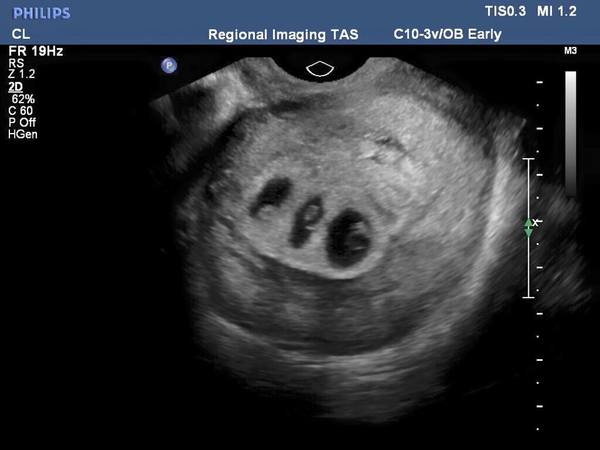

Kendisini şok eden haberle karşılaştı. Meğerse üçüzleri olacakmış!